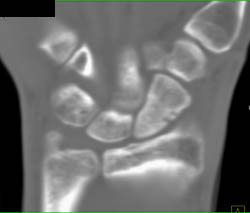

Diagnosis

Bone and Soft Tissue Metastases- and Liver and Adrenal Metastases- From Lung Cancer